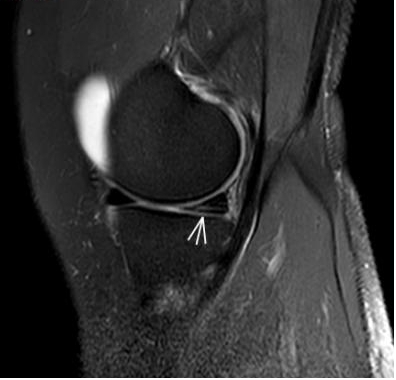

2. 运动后“打软腿”——韧带的“断弦危机”

场景:打球急停后膝盖不稳,走路像“踩棉花”

MRI侦查:揪出前交叉韧带断裂“波浪状”或连续性中断)、内侧副韧带损伤,防止关节“脱轨”

内侧副韧带损伤)